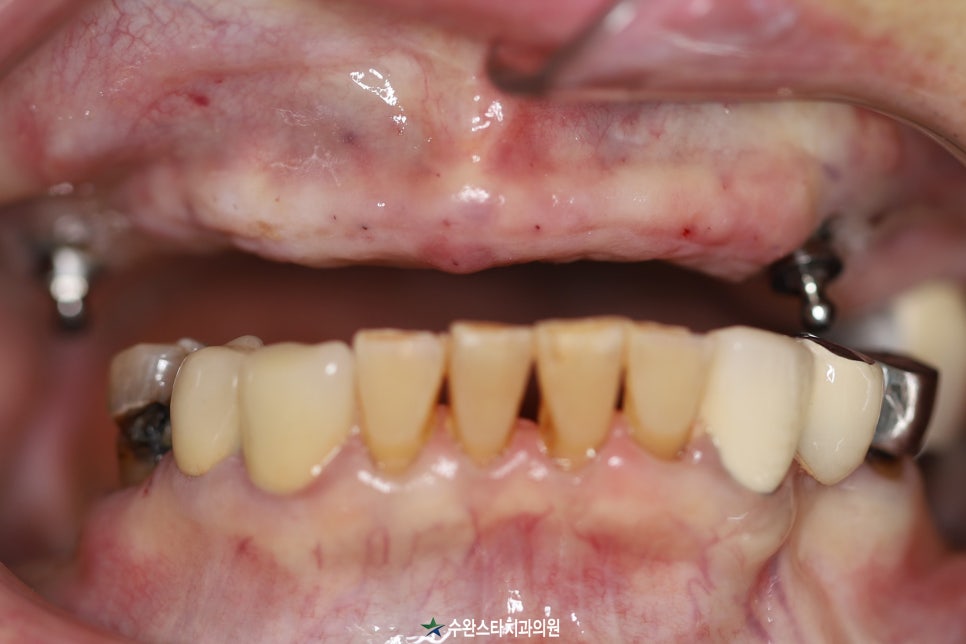

수술 후 3일 경과 임시치아, (2024/6월 촬영)

수술 후 3일 만에

실도 빼기 전에

치아 넣어드렸습니다.

수술 전 / 수술 후 (2024/6월 촬영)

치아를 넣어드린 덕분에

환자분께서

"6년 동안 치아 때문에

고생이 너무 많았는데

이제는 먹는 것도 수월하고

혀도 안 씹혀서 좋아요.

이렇게 수술 하고 나서

3일 만에 바로 치아를 넣어준다는 게

대단하네요.

너무 감사합니다."

라며 감사의 말씀을 전하셨습니다.